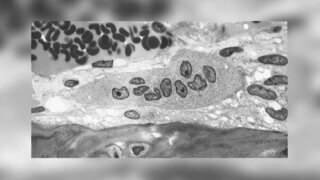

Pilotstudie zur Knochenregeneration nach ExtraktionWie wirken sekundäre Pflanzenstoffe bei der Knochenheilung? Sekundäre Pflanzenstoffe aus Traubenkern- und Grapefruitextrakten gelten als Antioxidanzien und wirken entzündungshemmend. Doch ist damit auch automatisch eine bessere Knochenregeneration verbunden? 14.09.2020 ZahnmedizinChirurgie